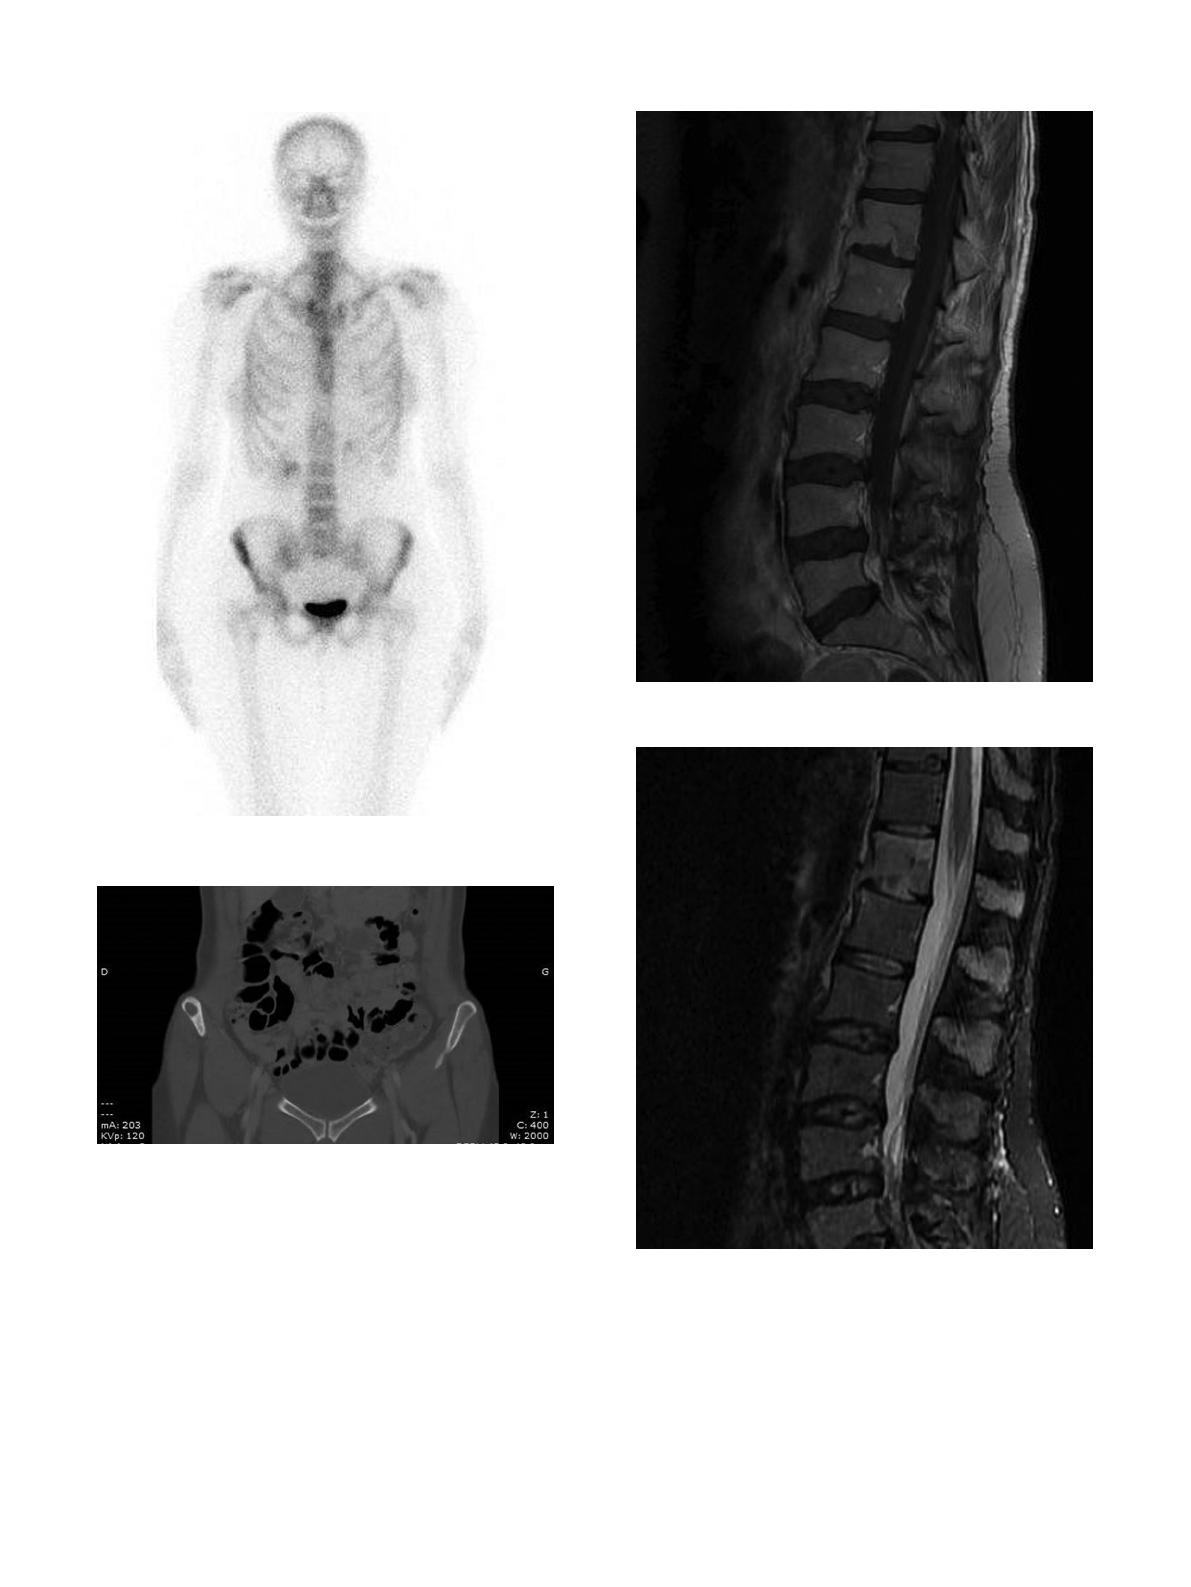

La

scintigraphie

osseuse

montre

une

hyperfixation

aspécifique

(Fig.

4).

Le

scanner

5)

et

l’IRM

apportent,

de

fac¸

on

inconstante,

des

signes

orientant

vers

infection

chronique

:

abcès

parties

molles,

calcifications

dans

les

séquestre

osseux.

Fig.

4.

Ostéite

tuberculeuse

iliaque

;

scintigraphie.

5.

iliaque,

même

patient

scanner.

6.

Spondylodiscite

T12-L1

IRM

séquence

T1

avec

gadolinium.

7.

T2

STIR.